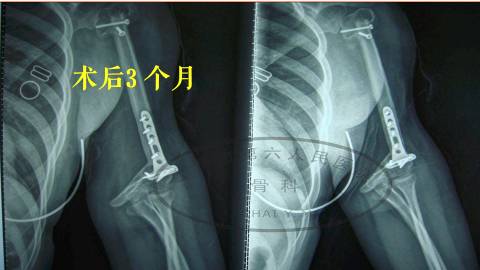

手术后三个月,骨折得到愈合。

从术前和术后的比较看,我们看左上肢得到了明显的延长。

更重要的是,这个小孩恢复了她上肢的支撑功能,所以三个月的时候,她可以上举,可以曲肘,可以梳头,可以吃饭这些动作,对她是比较有利的。